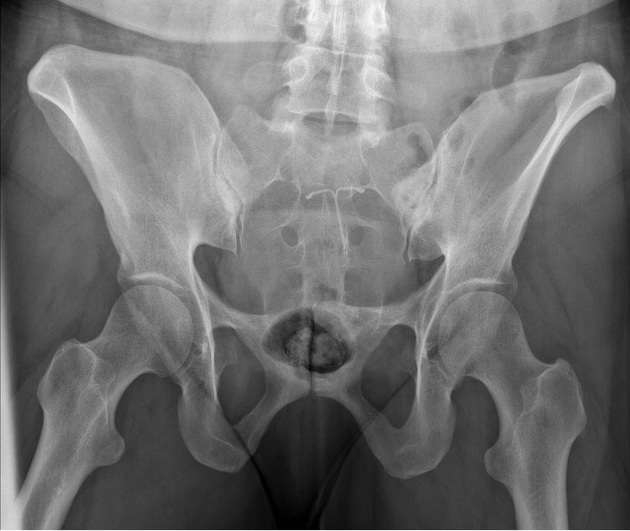

what view is this? what’s the tube angle?

pelvic inlet, 25-40° crawdad (ischial rami are perp to IR)

what view is this? tube angle

pelvic outlet , 30-45° cephy (ischial rami are parallel to IR)

what angle for both Judet hips (typical)

45°

Judet hip - iliac view

affected/unaffected side of the pelvis is rotated 45 degrees anteriorly, allowing visualization of the 1 and 2

1 - posterior column, 2 anterior wall and rim

Judet obturator view

unaffected/affected side of the pelvis is rotated 45 degrees anteriorly, allowing visualization of the 1 and 2

affected

obturator ring, posterior wall